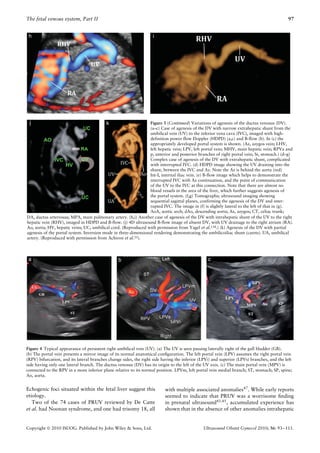

Figure 3 (Continued) Variations of agenesis of the ductus venosus (DV).

(a–c) Case of agenesis of the DV with narrow extrahepatic shunt from the

umbilical vein (UV) to the inferior vena cava (IVC), imaged with high-

definition power flow Doppler (HDPD) (a,c) and B-flow (b). In (c) the

appropriately developed portal system is shown. (Az, azygos vein; LHV,

left hepatic vein; LPV, left portal vein; MHV, main hepatic vein; RPVa and

p, anterior and posterior branches of right portal vein; St, stomach.) (d–g)

Complex case of agenesis of the DV with extrahepatic shunt, complicated

with interrupted IVC. (d) HDPD image showing the UV draining into the

shunt, between the IVC and Az. Note the Az is behind the aorta (red)

Int-I, internal iliac vein. (e) B-flow image which helps to demonstrate the

interrupted IVC with Az continuation, and the point of communication

of the UV to the IVC at this connection. Note that there are almost no

blood vessels in the area of the liver, which further suggests agenesis of

the portal system. (f,g) Tomographic ultrasound imaging showing

sequential sagittal planes, confirming the agenesis of the DV and inter-

rupted IVC. The image in (f) is slightly lateral to the left of that in (g).

AoA, aortic arch; dAo, descending aorta; Az, azygos; CT, celiac trunk;

DA, ductus arteriosus; MPA, main pulmonary artery. (h,i) Another case of agenesis of the DV with intrahepatic shunt of the UV to the right

hepatic vein (RHV), imaged in HDPD and B-flow. (j) 4D ultrasound B-flow image of absent DV, with UV drainage to the right atrium (RA).

Ao, aorta; HV, hepatic veins; UC, umbilical cord. (Reproduced with permission from Yagel et al.134.) (k) Agenesis of the DV with partial

agenesis of the portal system. Inversion mode in three-dimensional rendering demonstrating the umbilicoiliac shunt (carets). UA, umbilical

artery. (Reproduced with permission from Achiron et al.55).